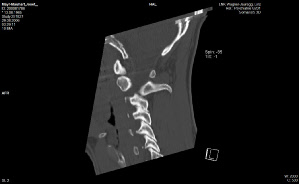

Anbei Daten zur Enthauptung (Heilige Schrift)

Jefferson Fraktur (med. Fachsprache)

Das Bild bekam ich erst vor kurzem

Ist vom 20.11.2017